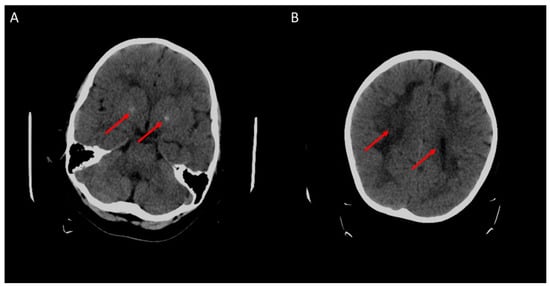

2. Case Presentation